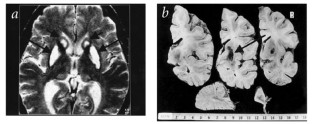

We describe here a previously unknown, dominantly inherited, late-onset basal ganglia disease, variably presenting with extrapyramidal features similar to those of Huntington's disease (HD) or parkinsonism. We mapped the disorder, by linkage analysis, to 19q13.3, which contains the gene for ferritin light polypeptide (FTL). We found an adenine insertion at position 460–461 that is predicted to alter carboxy-terminal residues of the gene product. Brain histochemistry disclosed abnormal aggregates of ferritin and iron. Low serum ferritin levels also characterized patients. Ferritin, the main iron storage protein, is composed of 24 subunits of two types (heavy, H and light, L) which form a soluble, hollow sphere1. Brain iron deposition increases normally with age, especially in the basal ganglia, and is a suspected causative factor in several neurodegenerative diseases2 in which it correlates with visible pathology3, possibly by its involvement in toxic free-radical reactions4. We found the same mutation in five apparently unrelated subjects with similar extrapyramidal symptoms. An abnormality in ferritin strongly indicates a primary function for iron in the pathogenesis of this new disease, for which we propose the name 'neuroferritinopathy'.